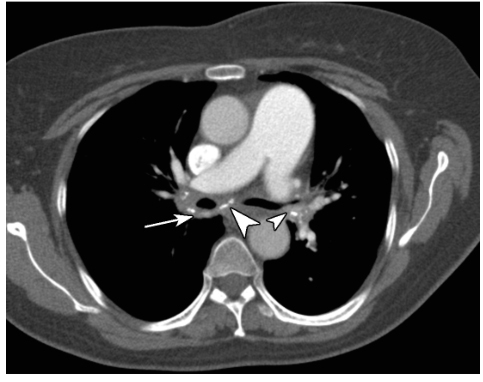

少见,多由组织胞浆菌病、结核感染所致,也可由急性纵隔炎发展而成,常见于前纵隔,病理上主要表现为肉芽肿、纤维化或两者并存,可分为纤维性纵隔炎(硬化性纵隔炎)和肉芽肿性纵隔炎。影像学大多表现为纵隔内肿块影和周围组织如气管、食管和血管的包绕压迫性改变(图1)。

图1 慢性纵隔炎

患者,女,59岁,胸部CT增强扫描纵隔窗示纵隔隆突下及双肺门区多发软组织密度影(白箭),内伴多发斑点状钙化(白箭头),病变包绕双侧支气管及肺动脉;肺动脉主干增宽,提示肺动脉高压。